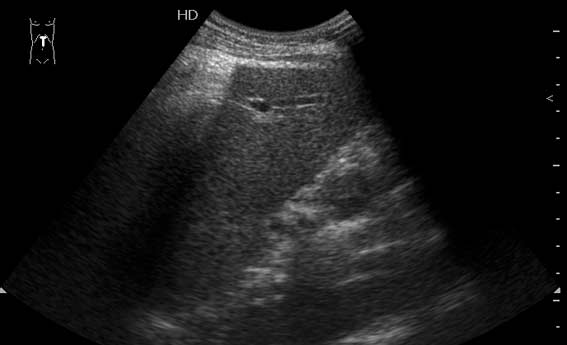

Свободный воздух в бршной полости, абдоминальное УЗИ

Заболел 3 часа назад.

Я пересмотрел видео (быстрое очень, кстати) видел в просвете аорты линейное эхо, принял за диссекцию. Тогда оставляю первую версию; свободный воздух в брюшной полости.

Действительно, так выглядит свободный воздух в брюшной полости при перфорации пологого органа - в данном случае - язвы дуоденум.